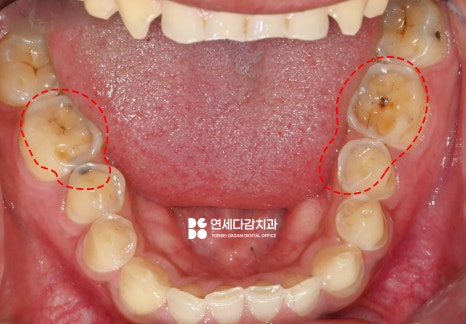

다만 해당 케이스는 환자가

불편한 부위만을 먼저

시행하는 것을 원했습니다.

그에 맞는 계획을 세우기 위해서

우선 치료할 부위를

정밀하게 검진합니다.

이렇게 이가 편평해질 정도로

교모된 곳을 우선 치료하게 됩니다.

충치가 있는 곳도 있었으나

치수에 도달할 정도로

심하게 진행된 상태는 아니었습니다.

따라서 문정동 치과 에서는

크라운 치료만으로

회복을 할 수 있었습니다.